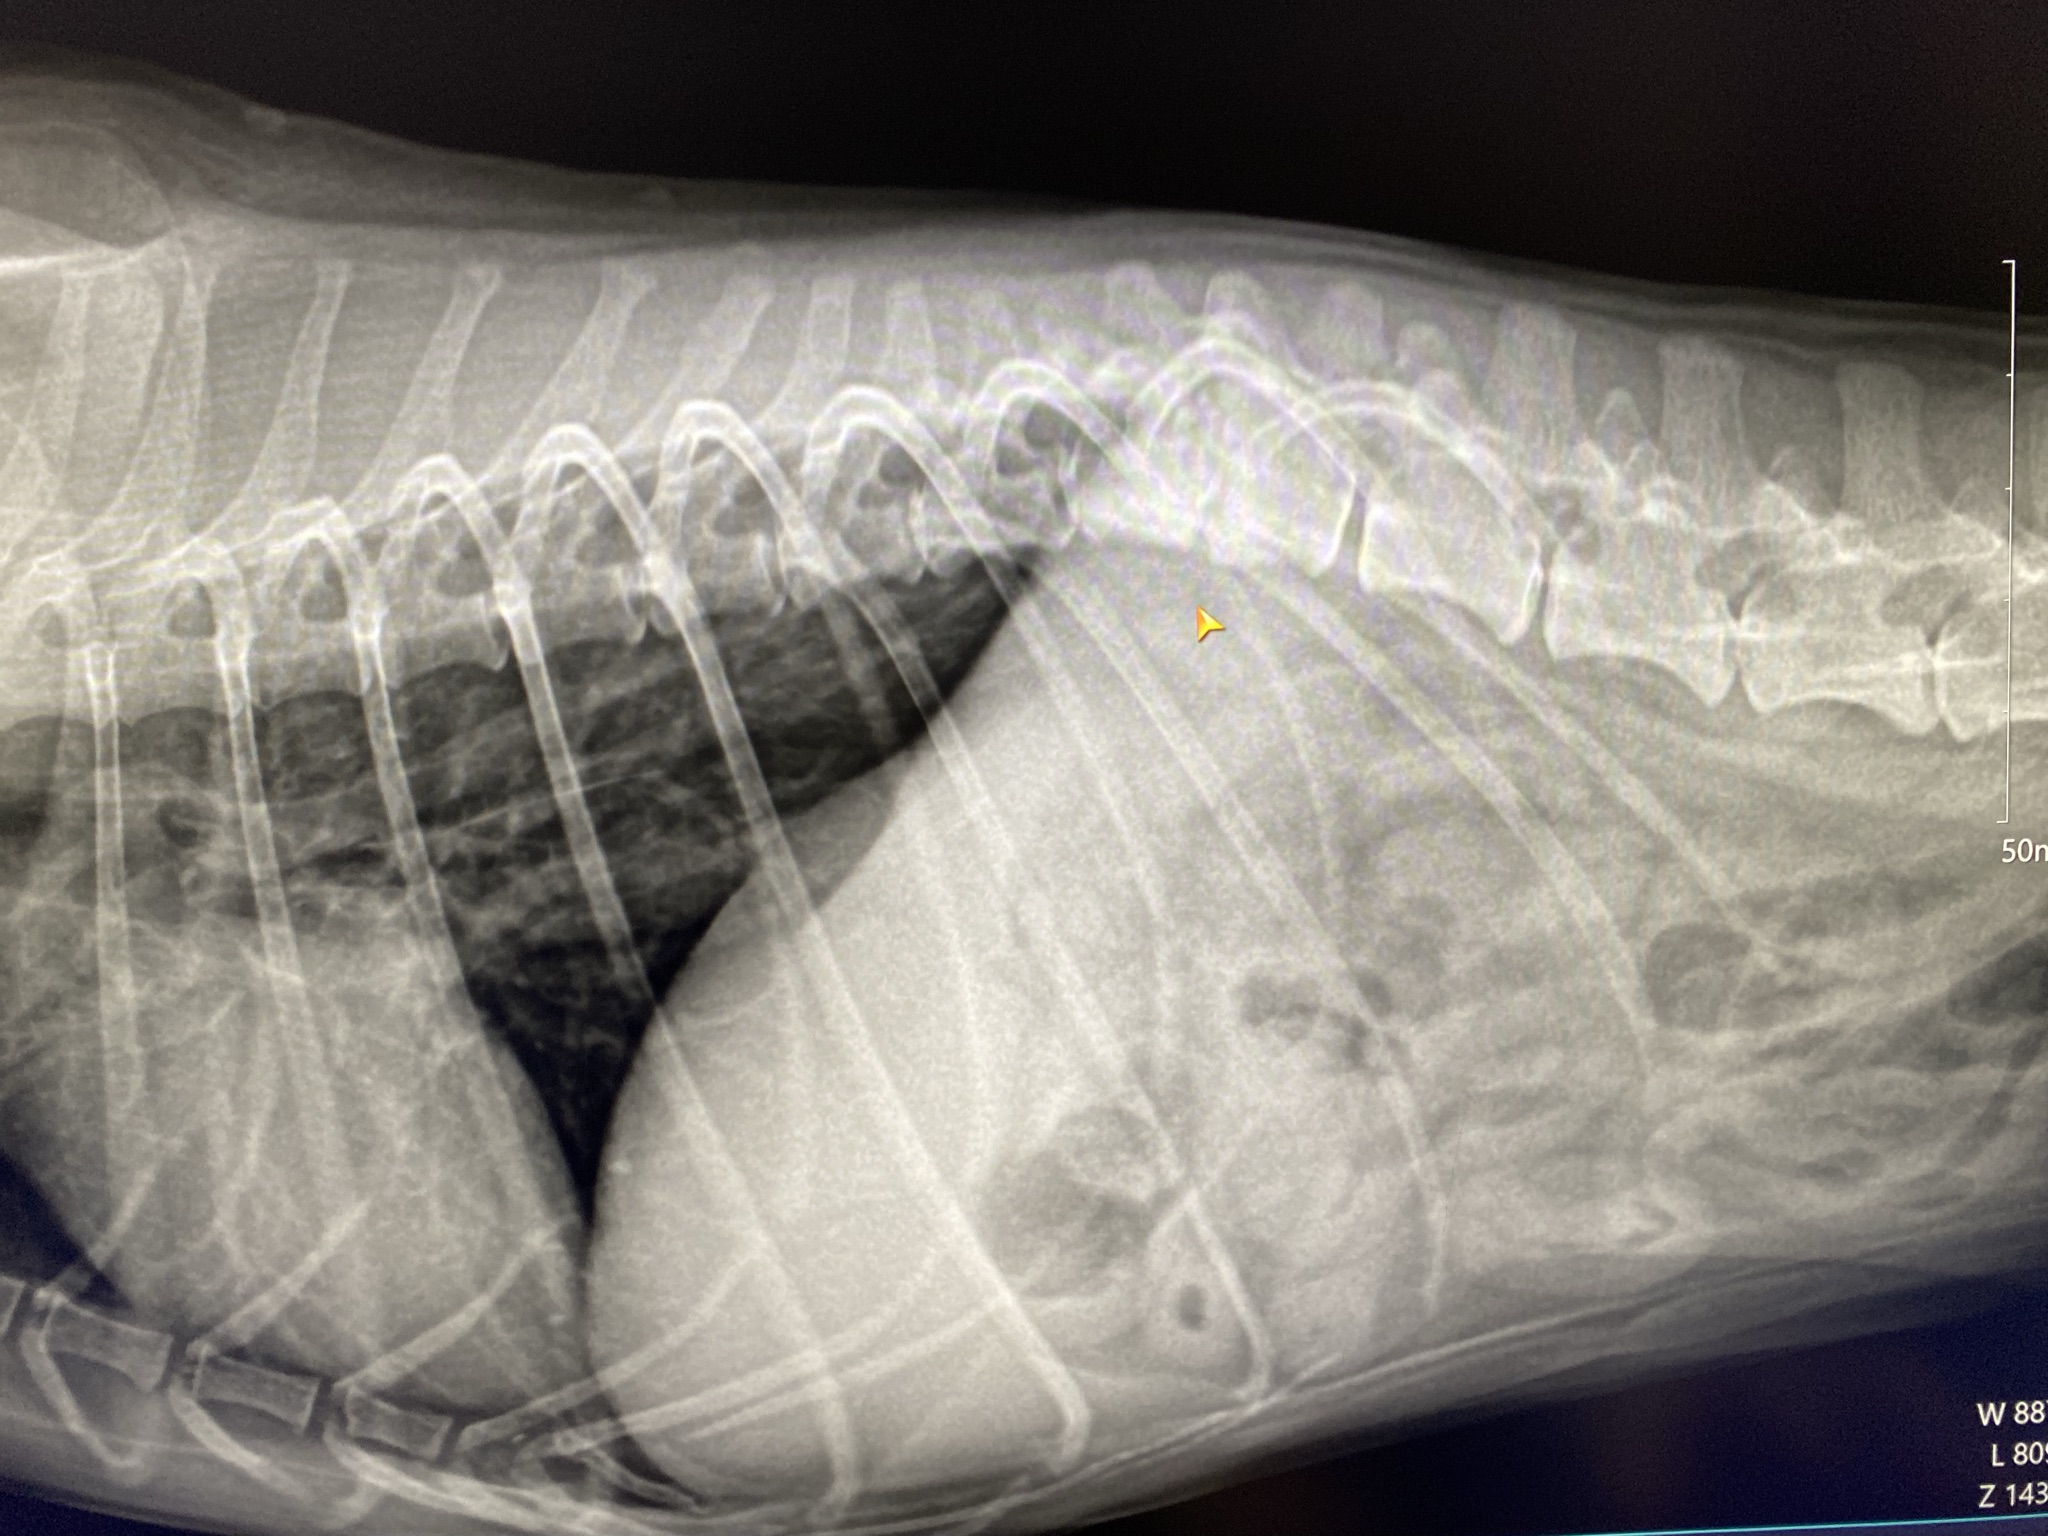

今回の学会の中では、尾追い行動に対して、問題行動あるいはてんかん発作を疑ったが実は馬尾症候群による疼痛による行動変化だったケース、

横になって眠ることができないことに対して、痛みや脳疾患を疑ったが、精神面が原因だったケースが紹介されていました。